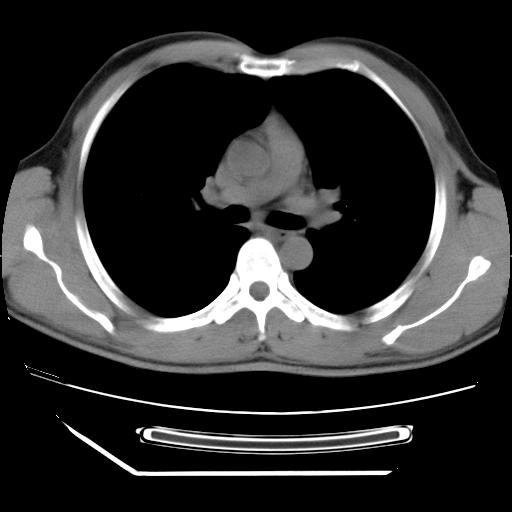

男,38岁,于2009年8月9日晚突发左侧胸痛,今x线提示左下肺阴影,为了明显确诊断,行ct检查,

血常规:嗜酸性细胞增高,单核细胞增高。

病灶发生在下叶,密度均匀,边缘模糊、毛糙,周围血管纹理增强扭曲改变,靠近胸膜处病灶胸膜反应明显。

支持考虑---球形肺炎。

左肺舌叶病变。主体病灶呈类圆形中心密度低,成液化趋势周边班片影分布

考虑肺脓肿

虽然实验室检查支持炎性病变,且病变内有坏死改变(中央呈大片状低密度影),但仍不能掉以轻心,鳞癌也可以有这种影像改变。